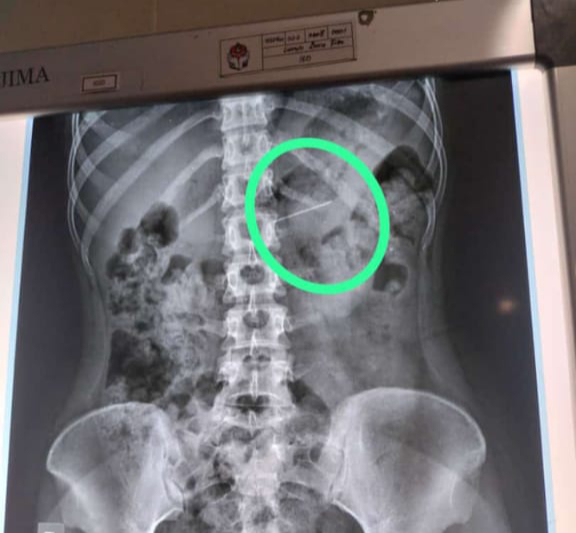

Warga Playen Menelan Jarum Pentol Pada Saat Memakai Jilbab